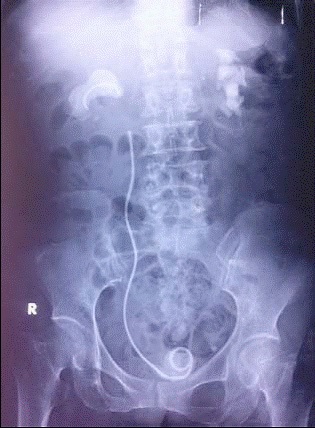

Trường ĐH Y Dược TPHCM cho biết vừa phát hiện hàng chục trường hợp người bệnh bị bỏ quên ống thông nhựa (JJ) trong cơ thể sau phẫu thuật kéo dài cả gần cả chục năm. Bỏ quên ống thông JJ là bệnh cảnh phức tạp, hiếm gặp, thống kê trên y văn chiếm tỉ lệ thấp. Do việc bị bỏ quên này trong người bệnh nhân đã gây nhiều biến chứng nặng nề cho người bệnh.

Theo ThS. BS Nguyễn Vĩnh Bình (Trường Đại học Y Dược TP HCM), từ năm 2011 đến 2014, nhóm nghiên cứu của ông đã ghi nhận được 24 trường hợp nhập viện Bệnh viện Chợ Rẫy do bị biến chứng bỏ quên ống thông JJ. Trong đó, thời gian bỏ quên “vật lạ” trung bình là 1,63 năm (có trường hợp bị bỏ quên ống này trong người suốt 8 năm), 9/24 trường hợp không biết sự tồn tại ống này trong cơ thể, 20/24 có sỏi bám ống thông, 8/14 bị nhiễm khuẩn đường tiết niệu, 6/24 biến chứng gãy ống thông… Dù các bác sĩ đã rút ống thông thành công nhưng có người bị choáng nhiễm trùng và đã tử vong.

Bác sĩ Bình cho biết thêm tại Việt Nam hiện nay, ống thông JJ được sử dụng hàng ngày là công cụ không thể thiếu đối với phẫu thuật tiết niệu. Tuy nhiên, trình độ dân trí thấp, thiếu sự dặn dò và cảnh báo biến chứng của thầy thuốc là nguyên nhân dẫn đến việc bỏ quên ống JJ. Vì vậy, cần phải có chương trình quản lý và giáo dục bệnh nhân tốt để giảm thiểu tình trạng bỏ quên thông JJ.